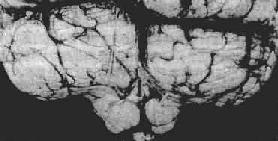

图16-8 小脑扁桃体疝 示小脑切迹,两侧扁桃体疝形成 (二)脑水肿 脑组织中由于液体过多贮积而形成脑水肿(brain edema),这是颅内压升高的一个重要原因。许多病理过程如缺氧、创伤、梗死、炎症、肿瘤、中毒等均可伴发脑水肿。 脑组织易发生水肿与下列解剖生理特点有关:①血脑屏障的存在限制了血浆蛋白通过脑毛细血管的渗透性运动;②脑组织无淋巴管以运走过多的液体。常见脑水肿的类型为: 1.血管源性脑水肿最为常见,是血管通透性增加的结果,当毛细血管内皮细胞受损,血脑屏障发生障碍时,或新生毛细血管尚未建立血脑屏障时(如转移性肿瘤及脑脓肿周围有大量的新生毛细血管),血液中的液体大量渗入细胞外间隙,引起脑水肿。白质水肿较灰质更为明显。此型水肿常见于脑肿瘤、出血、创伤或炎症时。水肿液较富于蛋白质。 2.细胞毒性脑水肿多见于缺血或中毒引起的细胞损害。由于细胞膜的钠-钾依赖性ATP酶失活,细胞内水、钠潴留,引起细胞(神经细胞、胶质细胞、内皮细胞)肿胀,细胞外间隙减小。此型水肿可同样累及灰质和白质。 上述两型水肿常同时存在,尤其在缺血性脑病时更为显著。 脑水肿的肉眼形态为脑体积和重量增加,脑回宽而扁平,脑沟狭窄,白质水肿明显,脑室缩小,严重的脑水肿常同时有脑疝形成。镜下,脑组织疏松,细胞和血管周围空隙变大,白质中的变化较灰质更加明显。电镜下,细胞外间隙增宽,星形胶质细胞足突肿胀(血管源性水肿),或无间隙增宽仅有细胞肿胀(细胞毒性水肿)。 (三)脑积水 脑脊液量增多伴脑室扩张称为脑积水(hydrocephalus)。脑积水发生的主要原因是脑脊液循环的通路被阻断。引起脑脊液循环受阻的原因很多,诸如先天畸形、炎症、外伤、肿瘤、蛛网膜下腔出血等。脑室内通路阻塞引起的脑积水称阻塞性或非交通性脑积水;如脑室内通畅而因蛛网膜颗粒或绒毛吸收脑脊液障碍所致的脑积水称交通性脑积水。此外脉络丛乳头状瘤分泌过多脑脊液也可导致脑积水。 轻度脑积水时,脑室轻度扩张,脑组织呈轻度萎缩。严重脑积水时,脑室高度扩张,脑组织受压萎缩、变薄,脑实质甚至可菲薄如纸,神经组织大部分萎缩而消失(图16-9)。

图16-9 脑积水 侧脑室高度扩张,脑组织受压萎缩变薄 婴幼儿颅骨缝闭合前如发生脑水肿,患儿可出现进行性头颅变大,颅骨缝分开,前囟扩大;颅内压增高较轻,头痛,呕吐,视乳头水肿也出现较晚。由于大脑皮质萎缩,患儿的智力减退,肢体瘫痪。成人脑积水,因颅腔不能增大,颅内压增加的症状发生较早也较严重。